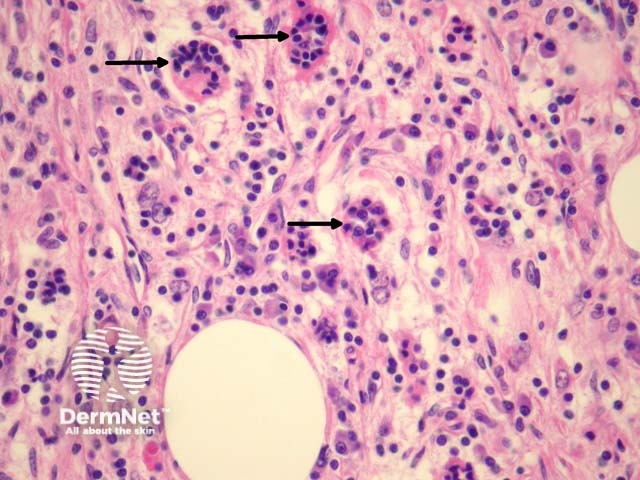

The hallmark of Rosai-Dorfman disease is emperipolesis, in which lymphocytes and other inflammatory cells reside undisturbed within the cytoplasm of the histiocytes (figures 3, 4, arrows).

Figure 4